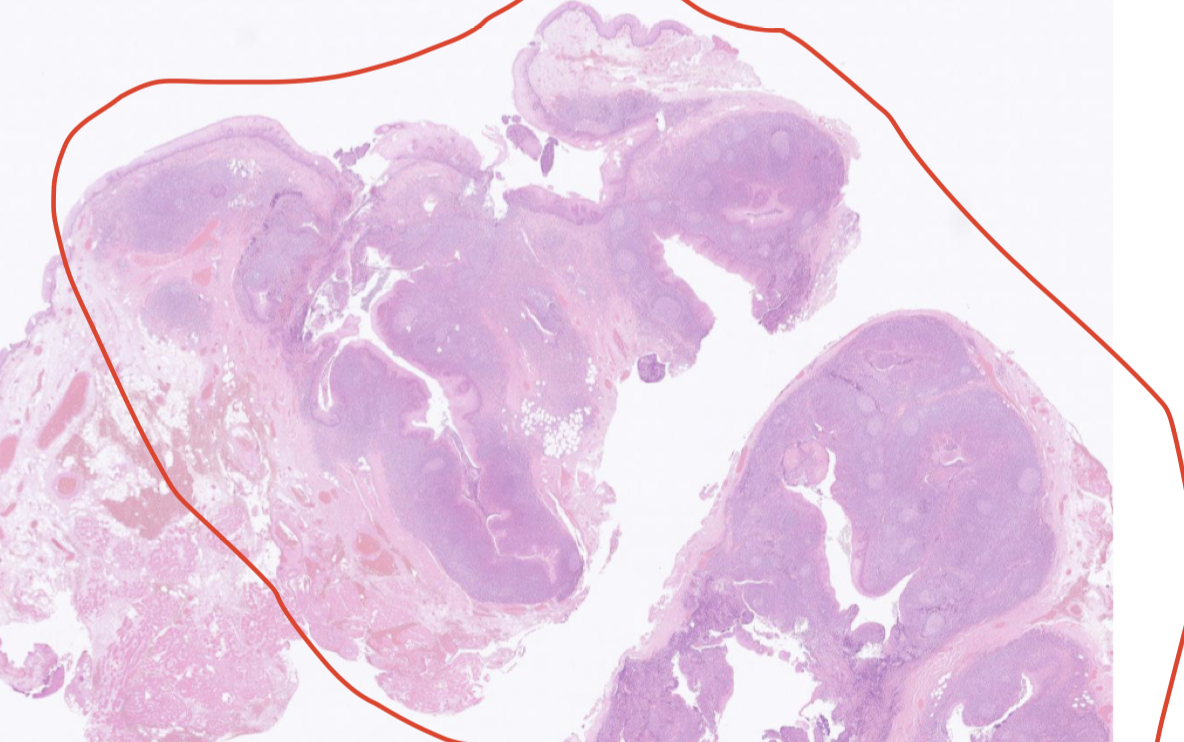

Vad är detta för organ?

Tonsill. En MALT.

Vilket epitel har tonsillerna?

Tonsillerna har skivepitel, det enda lymfoida organet med skivepitel. Finns ett lager med basalceller längst in.

Vad är en tonsillkrypta och vad finns där?

I en tonsillkrypta finns retikulärt epitel. Det är mer permeabelt för lymfocyter, i epitelet finns residenta lymfocyter.